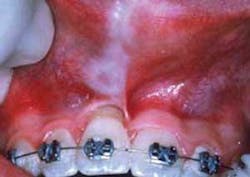

Constriction of oral tissues; patient with microstomia. Courtesy of Dr. T.D. Rees

Perioral and intraoral characteristics: Depending upon the extent of the disorder, the patient may exhibit constriction of the mouth (microstomia) and an inability to close the lips, due to the amount of fibrosis (see Figures 1 and 2). In Figure 1, a band of thick fibrotic tissue is evident on the lip extending to the wet line of the lip. In Figure 2, the skin and oral tissues are tight even with the aid of mirrors. Leader5 suggests a physical therapy technique used to increase the mouth opening over time: Lubricate the mouth, have the patient cross arms at chest height, with palms facing down, and use the thumbs to stretch the corners of the mouth for several minutes. Over time, the tissue may become more flexible. TMJ problems may be pronounced due to tissue constriction.